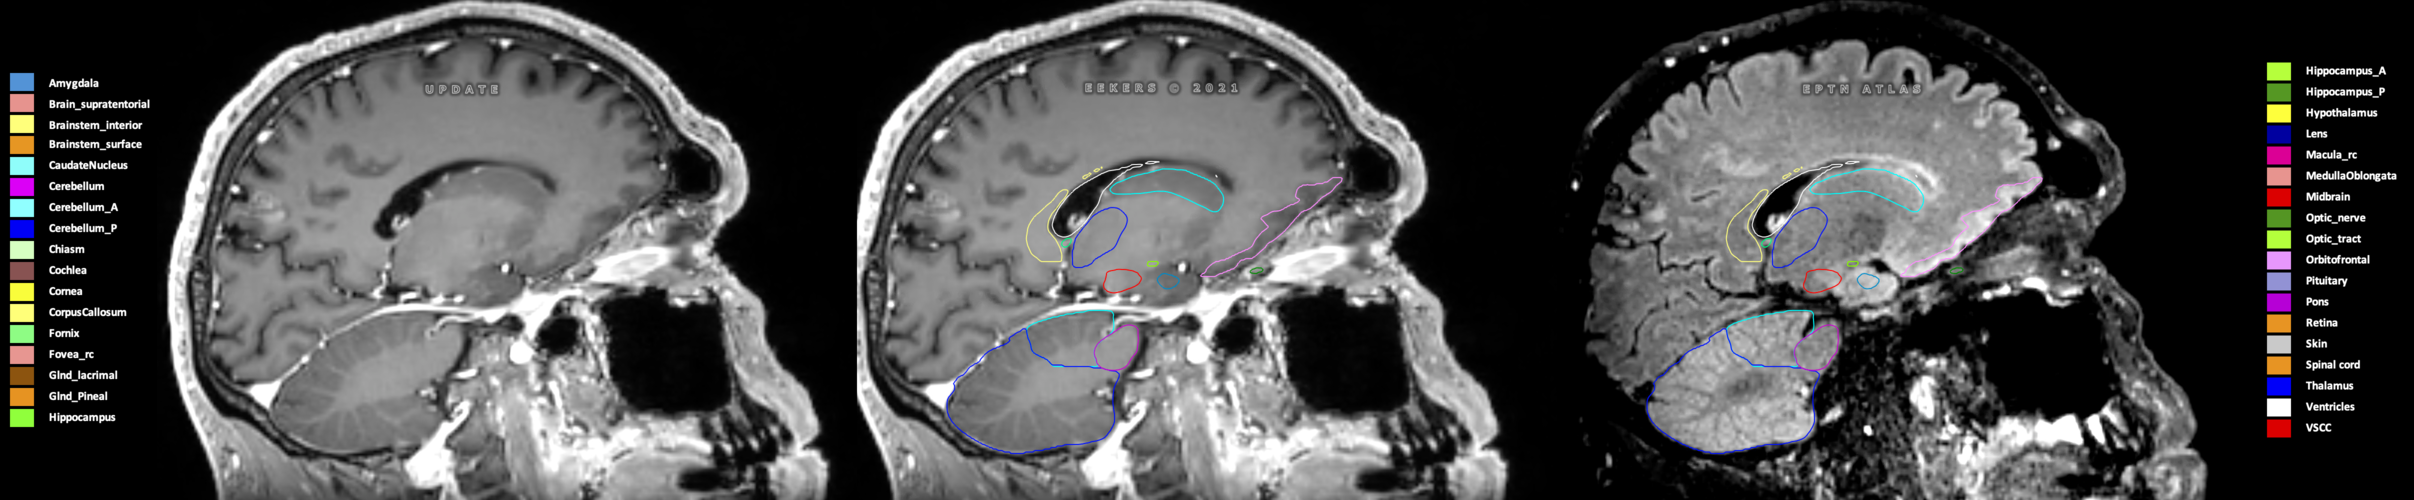

Eekers et al. have published an international neurological atlas for contouring of organs at risk in consensus with the European Particle Therapy Network (EPTN) in 2018 and an update in 2021. The purpose of this consensus atlas is to decrease inter- and intra-observer variability in delineating OARs relevant for neuro-oncology.

Included are all OARs known to be relevant for radiation-induced toxicity in neuro-oncology: brain, brainstem (midbrain, pons, medulla oblongata), chiasm, cerebellum (anterior & posterior), cochlea, cornea, hippocampus (anterior & posterior), hypothalamus, lens, lacrimal gland, optic nerve, pituitary, skin, and vestibular & semicircular canals. To further facilitate research on cognition, vision and radiological changes after irradiation of the brain, potential clinically-relevant OARs are included: amygdala, caudate nucleus, cerebellum (anterior & posterior), corpus callosum, fornix, macula, optic tract, orbitofrontal cortex, periventricular space (PVS), pineal gland, and thalamus.

Three-dimensional delineation of the 25 consensus OARs for neuro-oncology are shown on CT (WW/WL 120/40, 3000/600), 3T MR images, (T1Gd, T2FLAIR 1mm) and 7T MR (MP2RAGE 0.7 mm). All are presented in transversal, sagittal and coronal view.